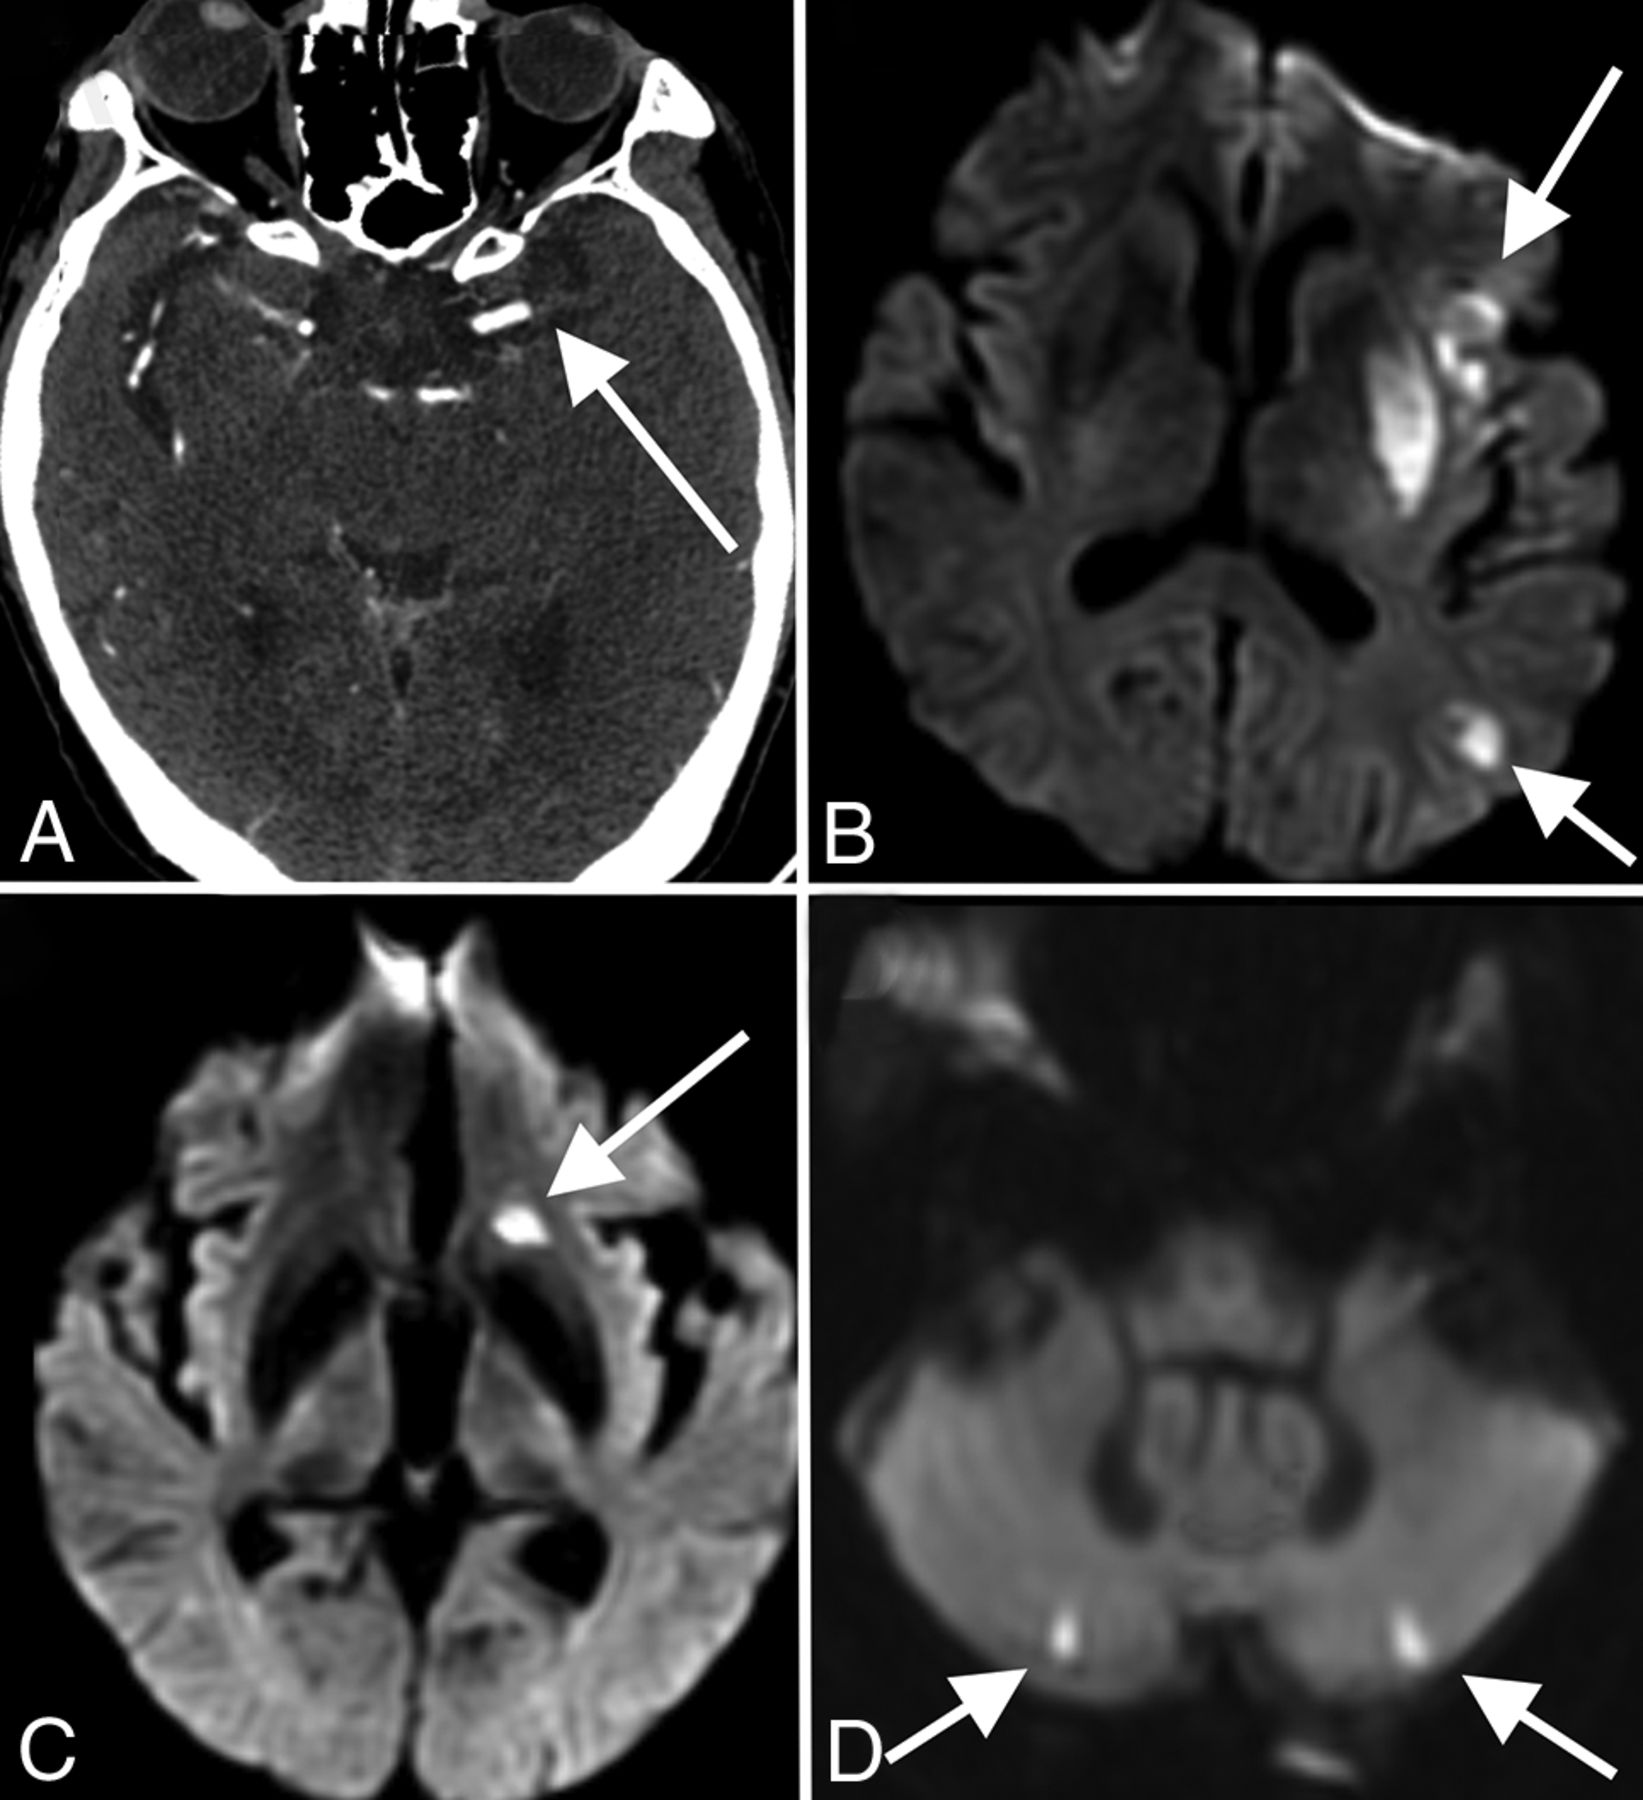

The 3 remaining patients with a greater burden of microhemorrhage had innumerable foci, predominantly involving the splenium of the corpus callosum, along with several foci along the remainder of the corpus callosum, internal capsules, and juxtacortical white matter (Fig 2). There were no foci involving the cortex, deep gray matter, brain stem, or cerebellum. The distribution in these 3 patients was atypical for both cerebral amyloid angiopathy and hypertensive microhemorrhage and, instead, was most compatible with critical illness–associated microhemorrhage.19,20 All 3 patients had prolonged intensive care unit courses with intubation and mechanical ventilation, but none were treated with extracorporeal membrane oxygenation. Two of the 3 had a history of hypertension, and none of the 3 had a history of seizures or antiepileptic medication use. One patient was receiving therapeutic enoxaparin (Lovenox) for deep vein thrombosis, while the other 2 patients were receiving prophylactic Lovenox at the time of imaging. Initial radiology reporting for 2 of these patients raised the possibility of diffuse axonal injury, but none of these patients had a trauma history. Following extubation, all 3 patients had clinical courses complicated by prolonged delirium and altered mental status. Of the patients with fewer than 15 foci of microhemorrhage, 2 additional patients also demonstrated foci only within the splenium of the corpus callosum.

Corpus callosum microhemorrhages. A 65-year-old woman (A), a 44-year-old woman (B), and a 69-year-old man (C) all demonstrate microhemorrhages on SWI, with a similar distribution, preferentially involving the corpus callosum (arrows in A–C), particularly the splenium. All patients had undergone mechanical ventilation before imaging. The distribution is similar to that previously described in critically ill, ventilated patients as well as in those with high-altitude cerebral edema.